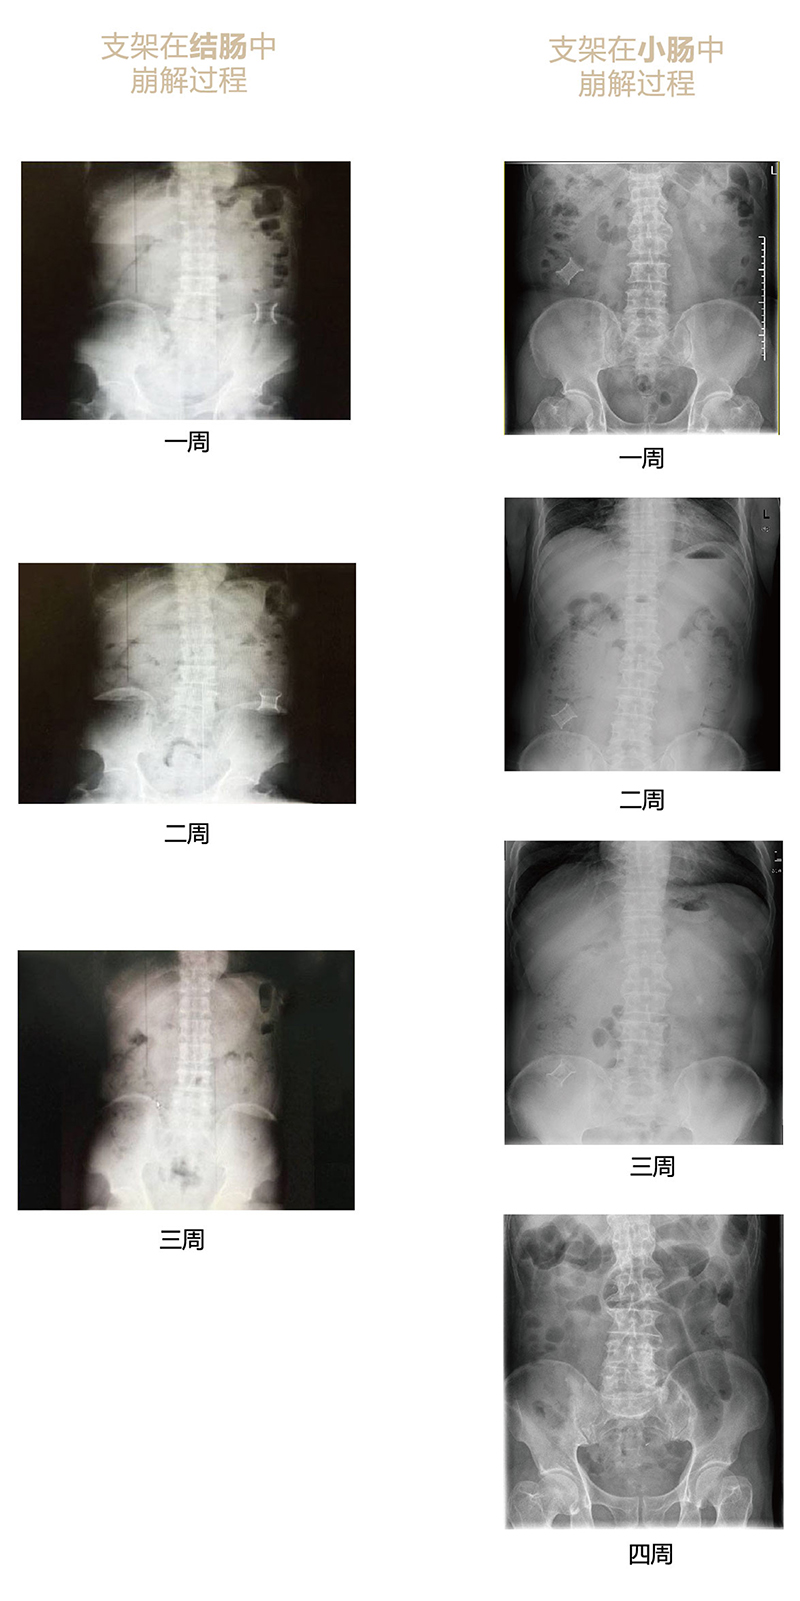

“可崩解腸道吻合器”由聚乙醇酸(PGA)與硫酸鋇按重量比7:1混合注塑制成,在X線下顯影,可動態(tài)追蹤可崩解腸道吻合器(支架)在腸道內(nèi)崩解過程。

為解決該問題,蔡秀軍教授在“支架法空腔臟器吻合技術(shù)”的理念基礎(chǔ)上,又發(fā)明了“蔡氏腸轉(zhuǎn)流術(shù)”,這是一種應(yīng)用“可崩解腸道吻合器HB型(可崩解腸轉(zhuǎn)流支架)”(發(fā)明專利號:201910794214.3),的支架法腸道轉(zhuǎn)流術(shù),此創(chuàng)新術(shù)式既能保護低位吻合口,更避免了回納術(shù)??杀澜饽c轉(zhuǎn)流支架在直腸癌根治術(shù)中植入遠端回腸,可確保完全阻斷腸腔,用腸造瘺管在轉(zhuǎn)流支架近端行腸造瘺,起到完全轉(zhuǎn)流的作用。腸轉(zhuǎn)流支架在二至三周內(nèi)逐漸崩解,并在四周內(nèi)完全排出體外,恢復(fù)腸道通暢后拔除造瘺管,避免了傳統(tǒng)造口回納的二次手術(shù)。該創(chuàng)新術(shù)式具有方法簡單、吻合時間短、人體內(nèi)無異物永久殘留、不破壞吻合口粘膜下血管,并能預(yù)防吻合口漏、可避免人工肛門留置及二次手術(shù)、治療周期可縮短至二至四周、患者生理心理創(chuàng)傷顯著減少。